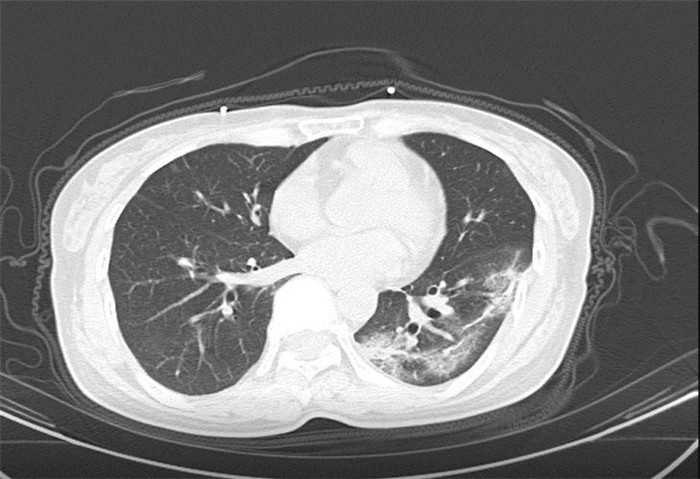

武漢大學(xué)中南醫(yī)院影像科副主任張笑春教授發(fā)現(xiàn),目前武漢市家庭聚集性發(fā)病較多,而且大多起病隱匿,一次甚至多次核酸陰性,無任何臨床癥狀,CT檢查卻已顯示為病毒性肺炎特征。

為了盡快篩查新型冠狀病毒肺炎患者,醫(yī)院會選擇影像診斷作為早期發(fā)現(xiàn)新型冠狀病毒感染的肺炎的重要一環(huán)。

CT為當(dāng)前首選篩查與診斷的主要影像學(xué)手段,胸部CT的病毒性肺炎檢出率高。

方舟CT(CT Ark)可以滿足全面的臨床功能,配置16層、32層、64層、128層CT,實(shí)現(xiàn)了低劑量掃描要求,配合NDI微劑量迭代技術(shù),智能毫安調(diào)控技術(shù),使各種場合下、各部位低劑量掃描得以實(shí)現(xiàn);超高分辨率CT病灶靶掃描,使病灶的密度顯示更加精確,能夠顯示病灶內(nèi)輕度的密度變化,有利于小病灶的密度定量分析和及時診斷。